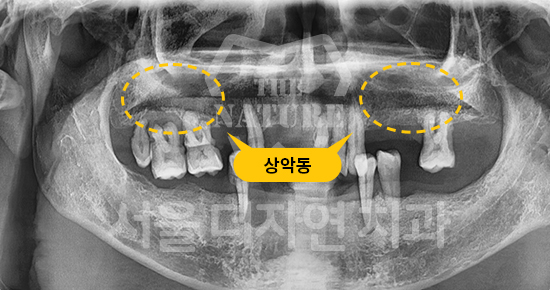

#Maxillary Bone Grafting

• BEFORE: 2021.11.02

• AFTER: 2022.01.19

Treatment outcomes may vary by patient,

and side effects may occur. These images were taken under the same conditions,

and were published with the patient's consent.